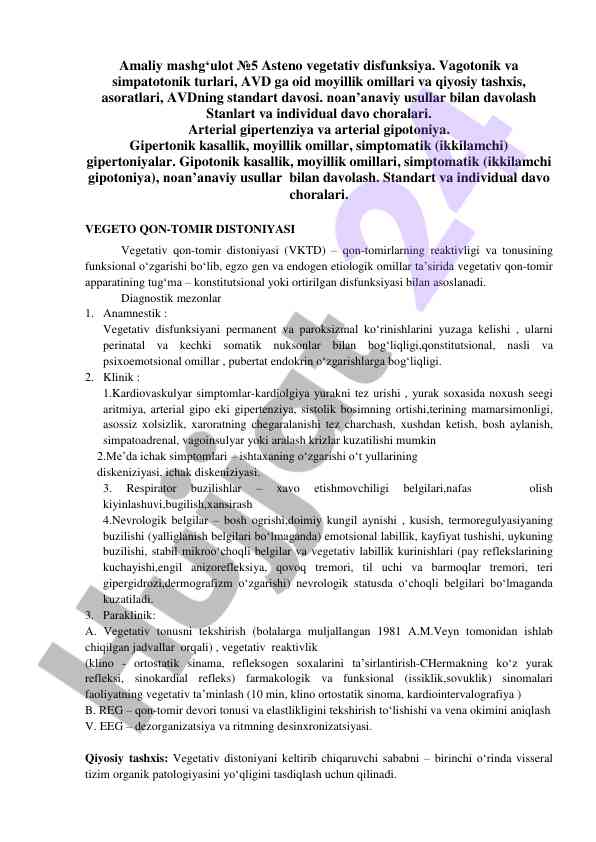

Данная лекция охватывает диагностические критерии, локализацию и структуру кист и опухолей челюстно-лицевой области, включая одонтогенные и неодонтогенные кисты.